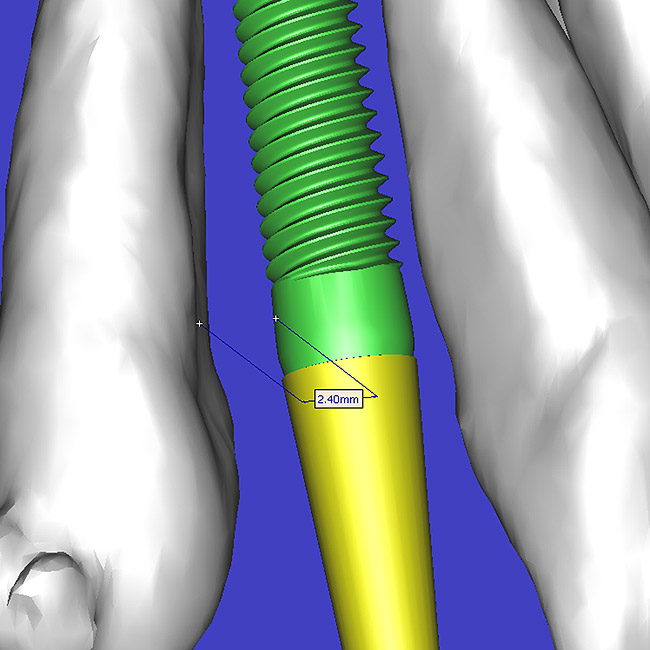

Using different masking (segmentation) and threshold Hounsfield unit values, several new 3D bone volumes can be created which offer invaluable information. To help determine the final position of each implant a new bone model was created with a Hounsfield unit value of 1480, which eliminated all but the densest objects included in the scan data. (Results may vary depending on the CBCT machine used.) The inner and outer layers of bone were removed, leaving the underlying enamel and root structure of the teeth (Figure 8A). After the bone had been stripped away, the root inclinations were examined closely. The most striking findings confirmed the rotated position of the right central, while revealing the slight mesial dilaceration of the root apex, which converged on the space needed for the path of the potential implant (Figure 8B). The schematic shapes of the proposed implants were visualized for the right and left lateral spaces in different rotations of the 3D maxillary arch. It was at this point that a determination was made as to the appropriate implant shape and type that would fit the available space while avoiding encroachment on adjacent tooth roots. A tapered design implant (Tapered Screw-Vent®, Zimmer Dental, www.zimmerdental.com) was chosen from the large virtual library. With the SIMPlant software, the virtual library contains data from dozens of implant manufacturers and realistic.computer-aided design representations as seen in Figure 9A through the translucent bone. The position of the left implant can be visualized with adequate mesial-distal distance between adjacent tooth roots (Figure 9B) and a more delicate placement (Figure 9C).

By using interactive treatment-planning software, the author was able to assess implant-to-tooth distances based on actual undistorted measurement of distances at both the crest (Figure 11A) and the apex (Figure 11B) of the implant. Additionally, the ability to section the 3D model allowed extremely accurate virtual implant placement, ensuring 2 mm of facial and palatal bone surrounding the implant (Figure 12A). Using advanced masking tools, further manipulation of the 3D maxilla provided an unparalleled appreciation not only of the potential implant receptor sites, but also of the alveolar.complex of each existing tooth and root morphology (Figure 12B).

Figure 9a  Virtual implants were placed to determine the appropriate shape and type for the available space, in this case a tapered design allowed for adequate mesial-distal distance between adjacent roots.

Figure 9a

Figure 9b  Virtual implants were placed to determine the appropriate shape and type for the available space, in this case a tapered design allowed for adequate mesial-distal distance between adjacent roots.

Figure 9b

Figure 9c  Virtual implants were placed to determine the appropriate shape and type for the available space, in this case a tapered design allowed for adequate mesial-distal distance between adjacent roots.

Figure 9c

Figure 11a  By zooming in on the digital image, the implant-to-tooth distances can be assessed at the (A) crest and the (B) apex.

Figure 11a

Figure 11b  By zooming in on the digital image, the implant-to-tooth distances can be assessed at the (A) crest and the (B) apex.

Figure 11b